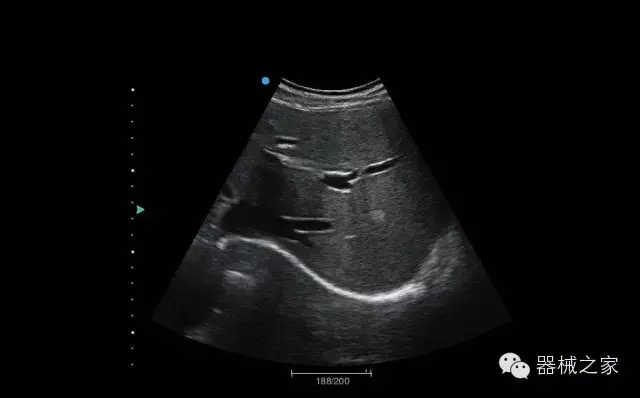

臨床圖片賞析

頸動(dòng)脈頻譜